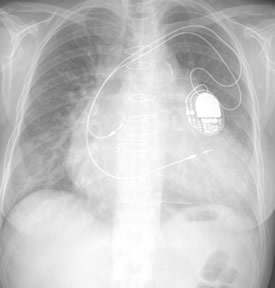

Lastly, this is an X-Ray showing the location and parts and where they are and where they go etc etc…